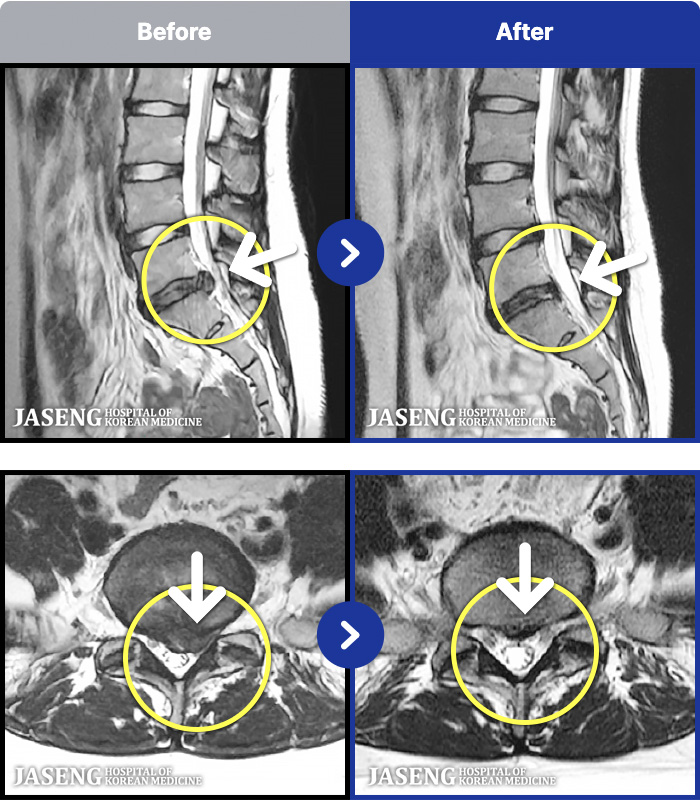

- MRI ġ

MRI ġ

1,237 MRI ũ ʸ Ȯϼ.

㸮 ϻ .